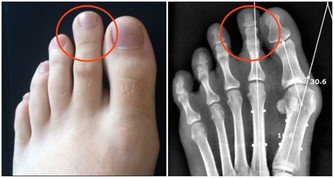

厲兌穴:在第二趾外側趾甲角旁約0.1寸。

隱白穴:位於足大趾末節內側,距趾甲角0.1寸處。